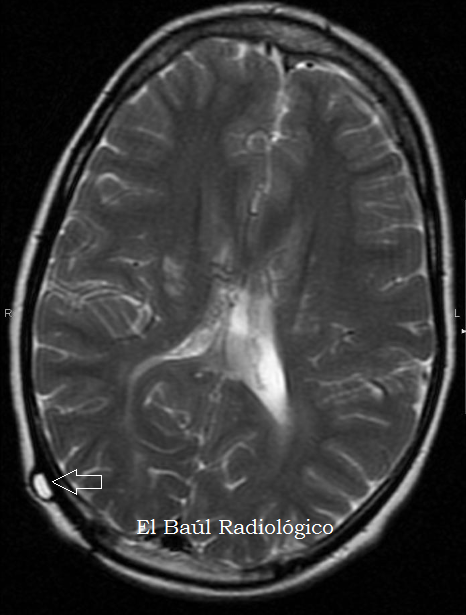

FIGURA 3) Estos catéteres de plástico no producen artefactos en las imágenes de IRM. Tan solo se aprecia la zona de entrada en el cráneo como si fuera una pequeña vesícula de líquido.

FIGURA 8) Desgraciadamente estas válvulas metálicas producen grandes artefactos oscuros por susceptibilidad magnética, cuando se realizan exploraciones de TRM (IRM) craneoencefálicas (flecha).